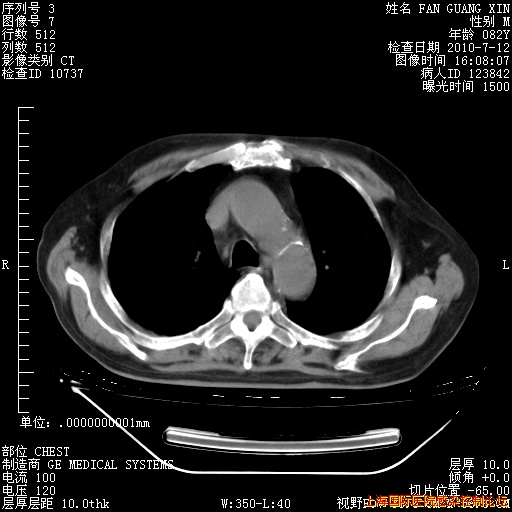

今天复查CT

今天CT

整整相隔30天的肺部CT好像有所好转啊。甲强龙减量第3天,需要观察体温。

海管,自昨日你和我通完话后,不知您岳父消化道症状有无缓解?体温怎样?阅读7.12日胸部ct,个人认为目前激素治疗是有效的,甲强龙减量是适宜的。因在抗痨治疗,需密切观察肝功、肾功能和血常规。不过,老年、长期住院和大量使用激素,很担心菌群失调发生